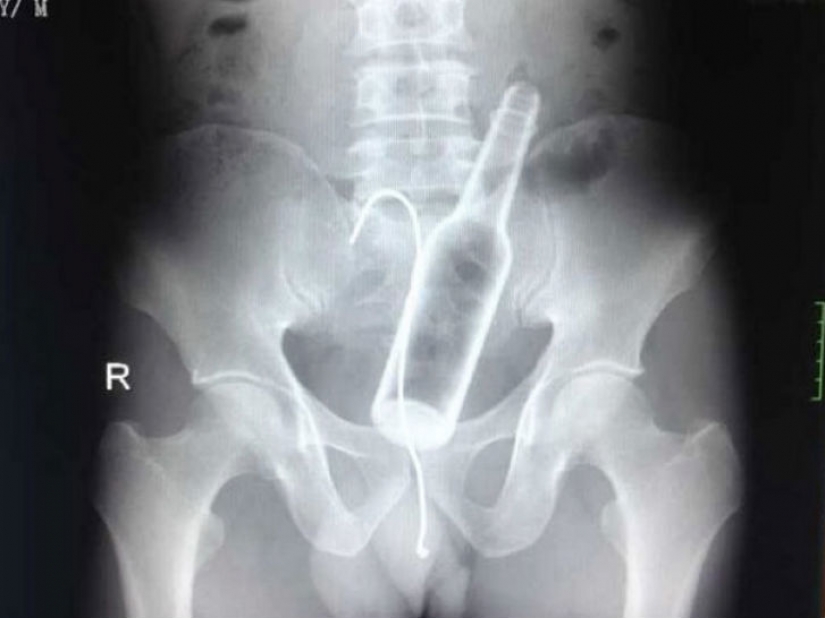

One of the Chinese hospitals, a man came with complaints of abdominal pain. The doctors took an x-ray and found a glass bottle in the stomach.